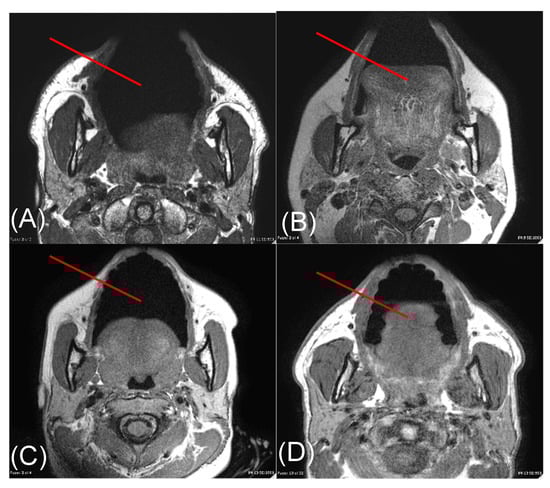

2.2. Volunteer MRI and Image Analysis

3.1. MRI and Image Analysis